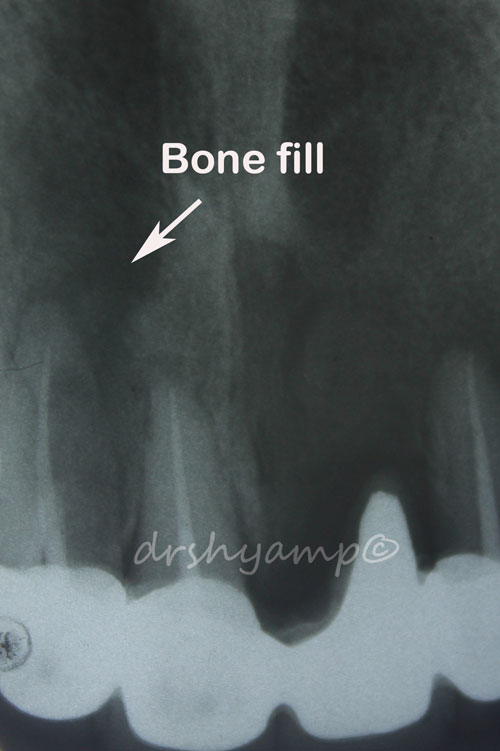

Periodontal flap surgery with bone grafting

Periodontal flap surgery with bone grafting

Periodontal flap surgery with bone grafting

Periodontal flap surgery with bone grafting

Periodontal flap surgery with bone grafting

Periodontal flap surgery with bone grafting

Periodontal flap surgery with bone grafting

Periodontal flap surgery with bone grafting

Periodontal flap surgery with bone grafting

Periodontal flap surgery with bone grafting

Periodontal flap surgery with bone grafting

Periodontal flap surgery with bone grafting

Periodontal flap surgery with bone grafting